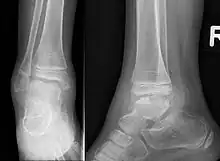

Trevor disease in a nine-year-old girl: talus | |

This disorder is rare, and is characterised by an asymmetrical limb deformity due to localized overgrowth of cartilage, histologically resembling osteochondroma. It is believed to affect the limb bud in early fetal life. The condition occurs mostly in the ankle or knee region and it is always confined to a single limb. This usually involves only the lower extremities and on medial side of the epiphysis. It is named after researcher David Trevor.[1]

Trevor disease was first described by the French surgeon Albert Mouchet and J. Belot in 1926. In 1956, the name "dysplasia epiphysealis hemimelica" was proposed by Fairbank.[1] The usual symptoms are the appearance of an osseous protuberance, on one side of the knee, ankle or foot joint which gradually increases Radiologically,[14] the condition shows a nonuniformity of growth and multiple unconnected ossification centers around the epiphyses.[8]